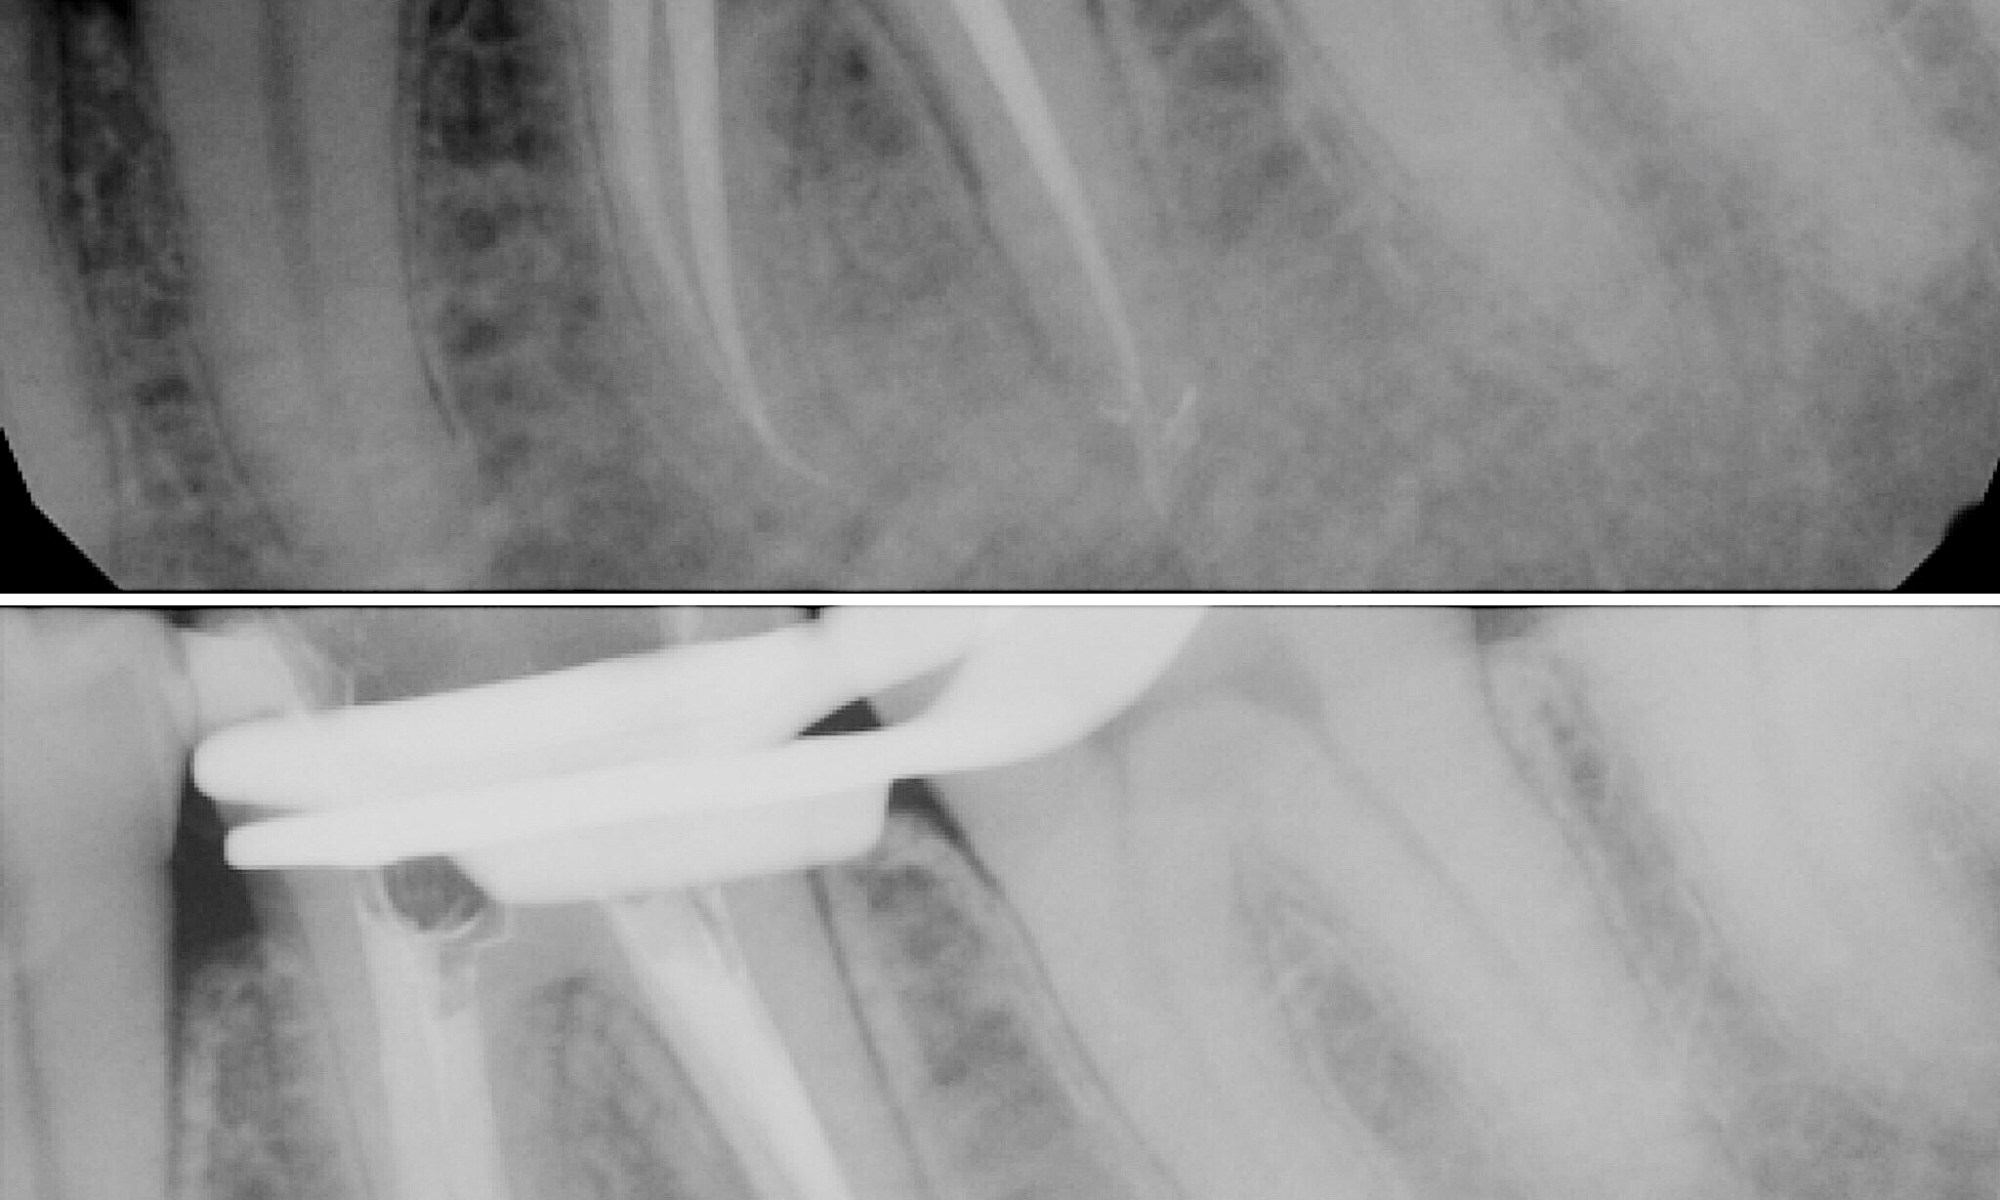

Root canal was completed previously, however, patient began to have symptoms again especially when she would eat. After examination to rule out cracked tooth syndrome, we discovered a small canal was missed and needed to be disinfected. This is an example of endo retreatment.